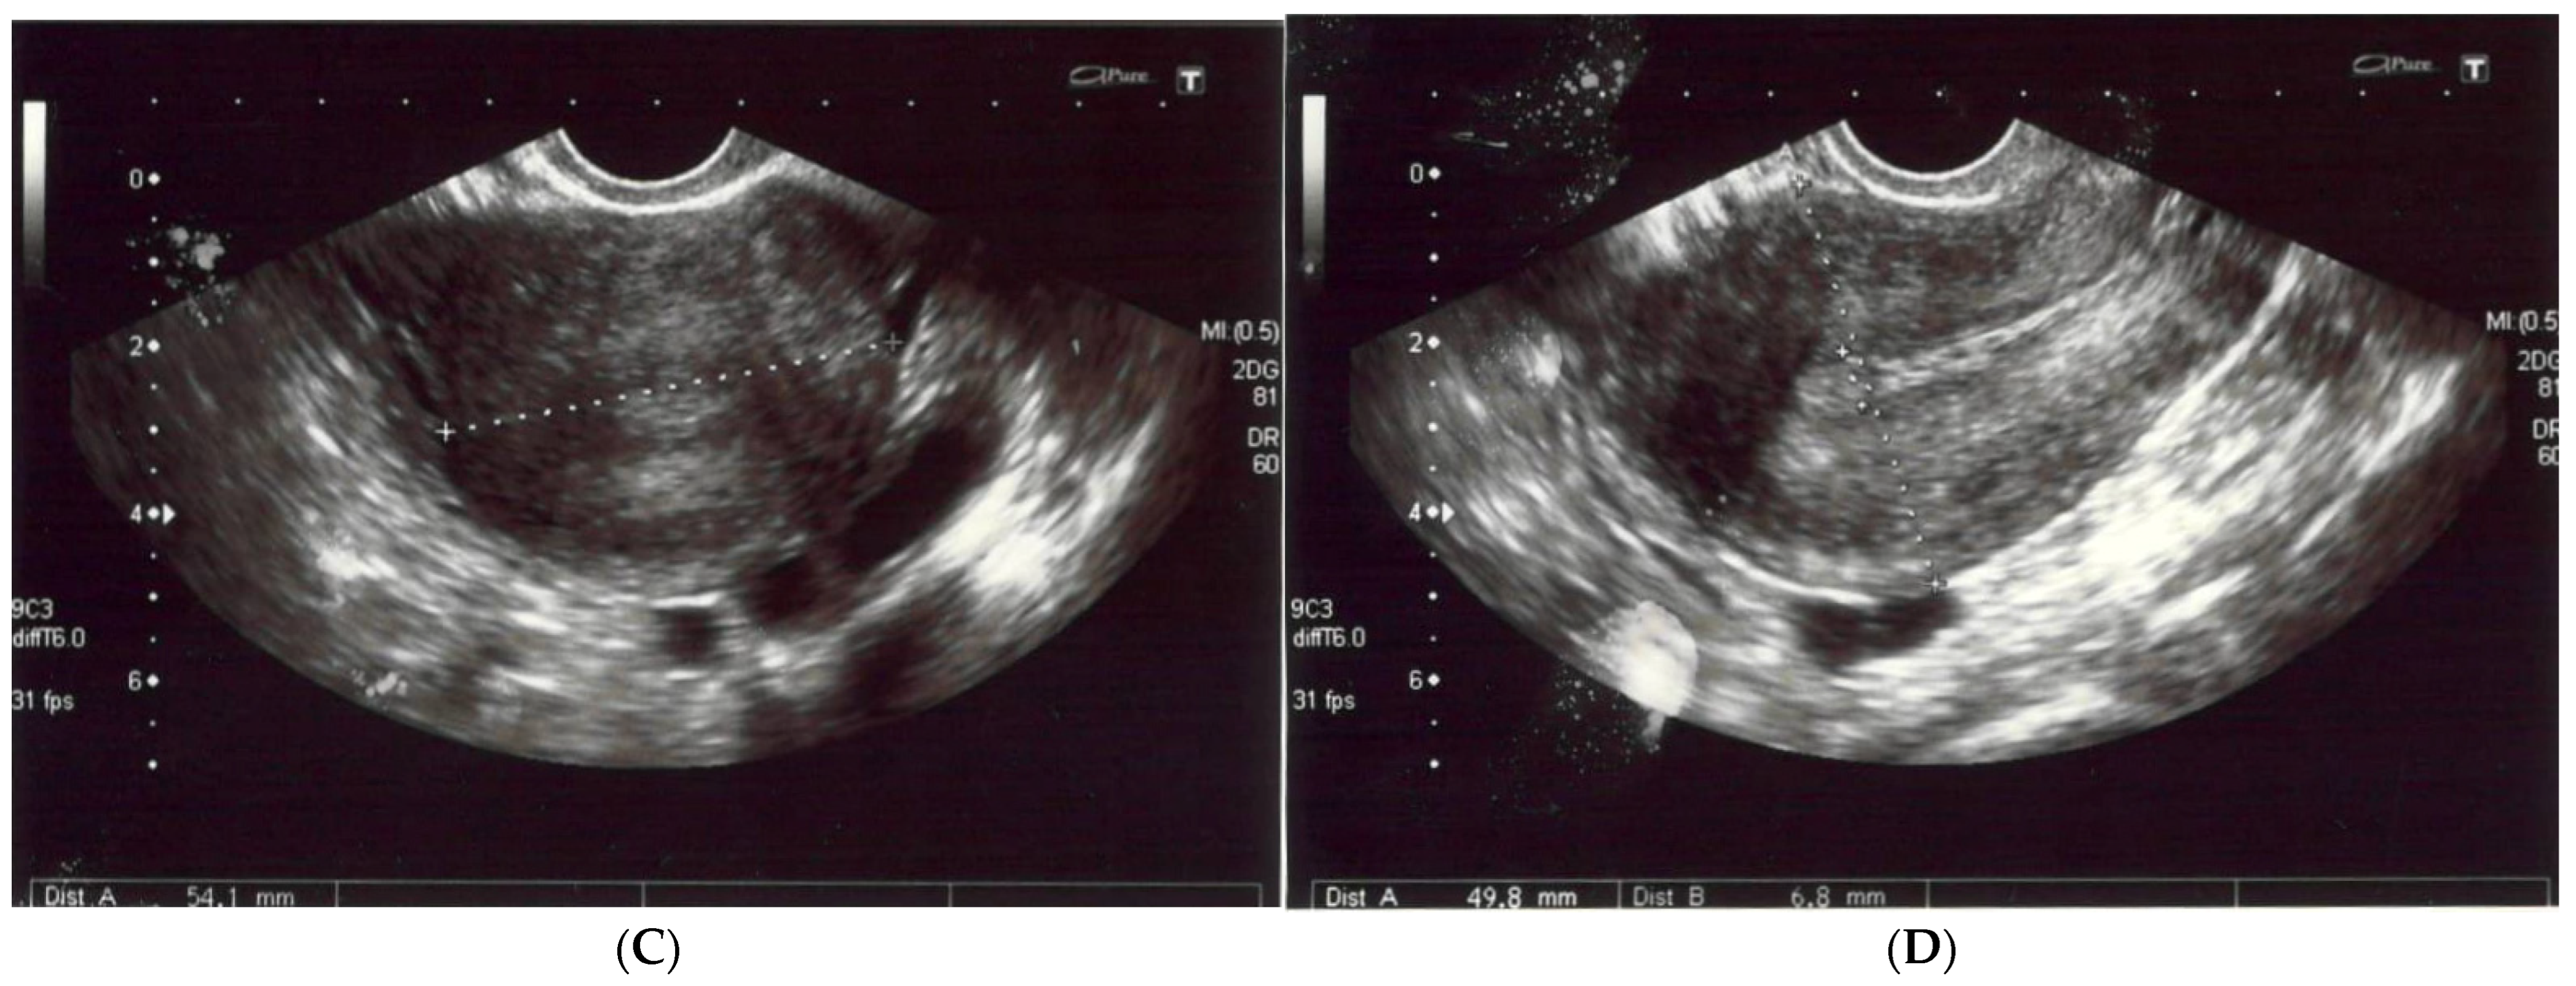

Histopathologically, there were non-atypical spindle cells with no mitotic activity or necrosis (Figure 3A).

Figure 3.

(A) The leiomyoma is composed of cells with elongated nuclei without cellular atypia (hematoxylin and eosin staining at a magnification of ×40 and ×200). (B) The immunohistochemistry for h-Caldesmon, which is positive in the leiomyoma cells (at a magnification of ×200). (C) The immunohistochemical staining for nuclear marker beta-catenin, which is negative in the leiomyoma cells (at a magnification of ×200). (D) The immunohistochemistry for smooth muscle antigen (SMA), which shows reactivity (at a magnification of ×200).

The immunohistochemistry reactions for the S100 protein, beta-catenin (Figure 3C), cytokeratin AE1/AE3, CD34 and progesterone receptor (PGR) were negative. The cell nuclei were negative for Ki-67, confirming their low proliferative potential. These results were typical of a benign tumor with smooth muscle differentiation; thus, the diagnosis of an intraosseous leiomyoma was established. Immunohistochemistry confirmed the absence of EBV in the pathological tissue.